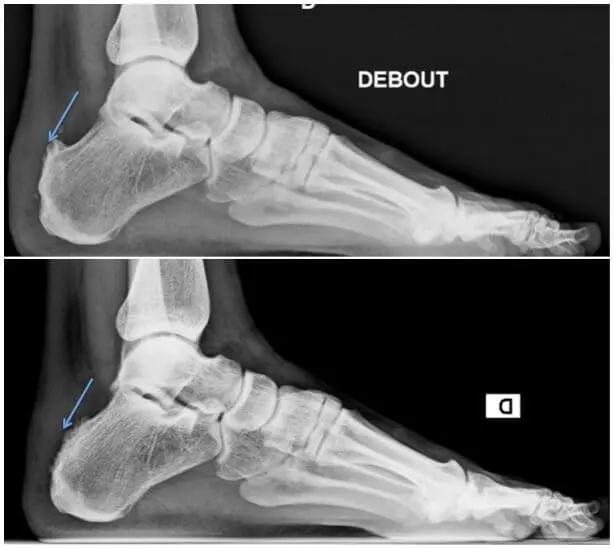

4. Haglund

On retrouve une bursite entre le calcanéum et le tendon d’Achille. La douleur est perçue un peu plus haut que l’insertion du tendon et un peu plus sur les côtés.

Causes

Cet espace, qui est normalement très fin, se voit enflammé et tuméfié par un frottement excessif.